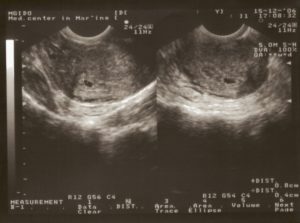

Также можно пройти УЗИ на 3 неделе беременности, если у вас есть подозрения. На этом сроке исследование проводится трансвагинальным датчиком.

УЗИ на 3 неделе беременности может показать (хотя вовсе не обязательно), где поселился эмбрион (то есть наступившая беременность развивается в матке или внематочно), а также сможет оценить состояние мышечной ткани матки, что имеет большое значение в прогностическом плане.

Чтобы преобразования начались, плоская лепешка свернулась, ее края соединились и образовали полую трубку. В этот момент начались ее волшебные превращения в эмбрион. Этому способствует активное деление тканей, что приводит к значительным изменениям плода.5 акушерская неделя соответствует 3 неделе со дня зачатия. Осмотр на УЗИ на 3 неделе беременности и фото, сделанное на современном аппарате в увеличенном виде, позволяют рассмотреть эмбрион, расположившийся в матке.

При помощи УЗИ на 3 неделе беременности уже можно диагностировать свершившееся зачатие и наличие плодного яйца в полости матки.

Ультразвуковое исследование покажет размер оплодотворенной яйцеклетки, которая уже прикрепилась к стенке матки, что поможет определить возраст зародыша и поставить акушерский срок беременности. У врачей существует специальная таблица, по которой можно определить срок беременности в зависимости от величины зародыша.

Плод на 3 неделе после зачатия имеет размер 4-5 мм в диаметре с учетом всех оболочек, которые его окружают. Плодное яйцо на этом сроке имеет вид каплевидного образования, которое заполнено жидкостью. Эмбрион настолько маленький, что при УЗИ его невозможно рассмотреть.Расположение плодного яйца чаще всего встречается в районе маточных труб (в одном из верхних углов матки). Но другие прикрепления оплодотворенной яйцеклетки не являются патологией.

УЗИ на третьей неделе беременности выполняется абдоминальным и трансвагинальным датчиком при наличии показаний.

В ряде случаев определение беременности методом УЗИ на раннем сроке до задержки менструации невозможно.

При УЗИ, выполненным на третьей неделе беременности, возможно определение следующих признаков.

- Утолщение эндометрия. Свидетельствует о готовности полости матки к имплантации эмбриона.

- Наиболее утолщенное место эндометрия. Является местом крепления зародыша.

- Желтое тело. Определяется прохождение овуляции и пролонгирование беременности.

- Мышечный тонус матки. Определение повышенного тонуса при слабом кровообращении в желтом теле могут являться признаком угрозы самопроизвольного выкидыша.

- Состояние маточных труб. При наличии утолщения в одной из них, это может быть признаком внематочной беременности с местом имплантации эмбриона в маточной трубе.

Неприятные ощущения или болезненность во время УЗИ должны отсутствовать.